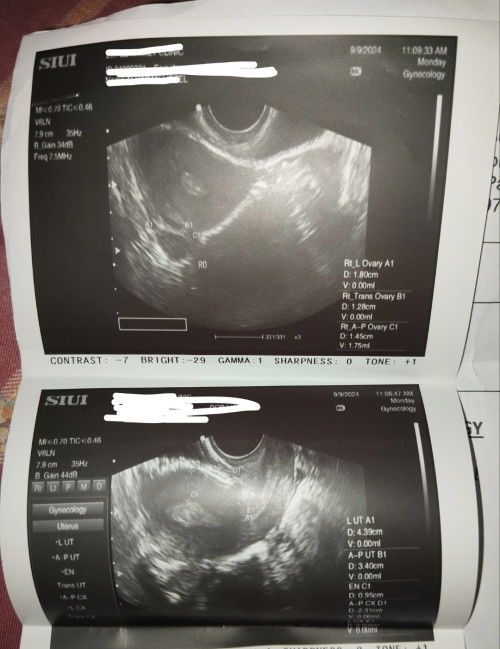

2 weeks delayed na ako nag pt ako positive,pero dinugo, yan nakita sa ultrasound, tas pt ako ulit weakly positive na siya🥺 may pag asa pa na mabuo? #help #preganancy

Magbasa paThickened endometrium. Baka starting pa lang po ang pregnancy or too early pa. Ano pi sabi ni ob? naiconsult nyo na ito sa kanya?